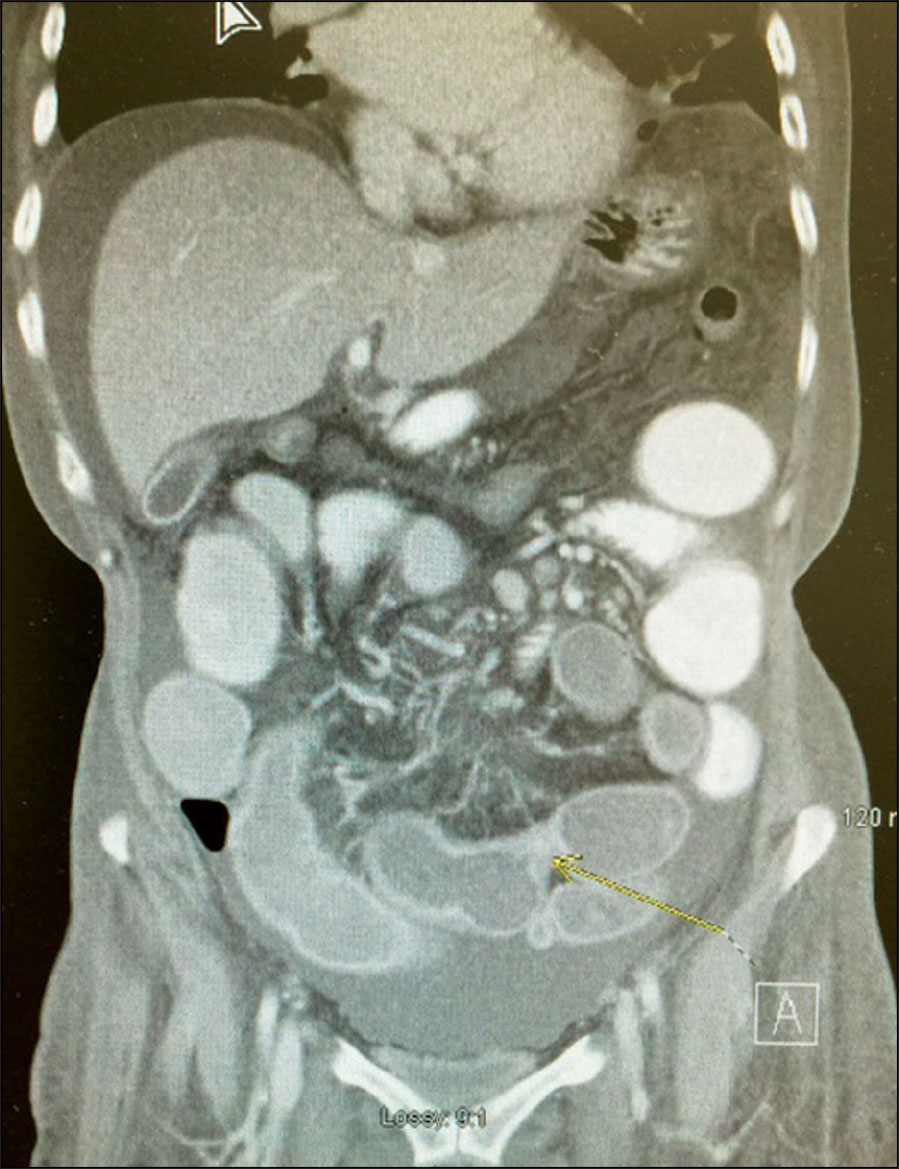

Unfortunately, she developed worsening pain at her right iliac fossa and a trial of intravenous steroid was given. She did not respond to the steroids and her repeat imaging showed evidence of small bowel obstruction and perforation (see Figure 1). Emergency laparotomy was performed and this showed dilated small bowel to the level of mid distal ileum. A stricture of small bowel was seen 40cm from ileocaecal valve with evidence of tiny perforations at ileum. Approximately 120cm in length of small bowel was resected (see Figure 2). The histology was consistent with a diagnosis of Crohn’s colitis, with fissuring ulcer and scarring of small bowel mucosa and transmural inflammation (see Figure 3). An anti-tumour necrosis factor (anti-TNF) blood screen was sent. She continued to have unremarkable post-operative recovery with nutritional support and engagement with physio-therapist. She was reviewed eight weeks later and was initiated on infliximab infusion.

Figure 1. CT abdomen/pelvis shows distended loops of mid small bowel (SB) with a transition from distended SB to normally distended SB and a transition from normally distended sb to collapsed bowel more inferiorly. Findings consistent with small bowel obstruction

Figure 1. CT abdomen/pelvis shows distended loops of mid small bowel (SB) with a transition from distended SB to normally distended SB and a transition from normally distended sb to collapsed bowel more inferiorly. Findings consistent with small bowel obstruction(click to enlarge)